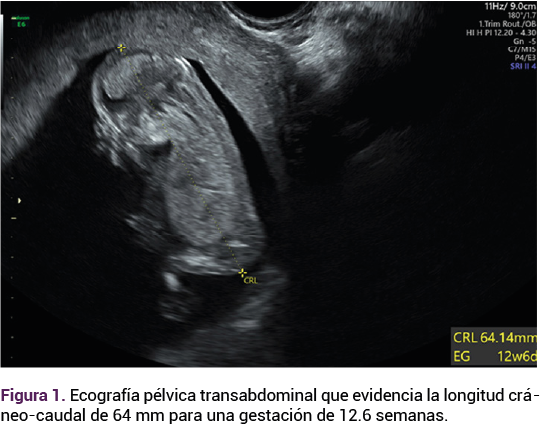

El ultrasonido pélvico transvaginal evidenció la existencia de un feto vivo de 12.6 semanas, por longitud cráneo-caudal (Figura 1), con discordancia de cavidades cardiacas ventriculares, comunicación intraventricular, ductus venoso patológico con onda invertida, translucencia nucal de 1.5 mm; placenta oclusiva total, con múltiples quistes en todo su espesor de 26 mm y vesículas a nivel placentario (imagen en “panal de abeja”) que corresponden a las vellosidades coriónicas marcadamente hidrópicas. Figura 2

<strong>Figura 2</strong>

Figura 2.